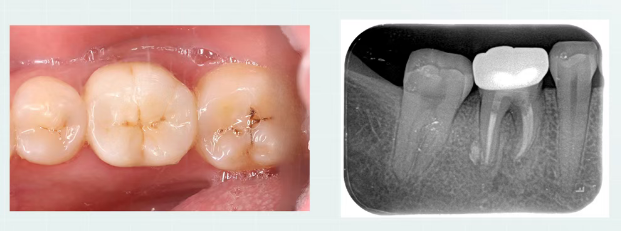

检查:颌面可见外院牙色充填物,颊侧黏膜可见一瘘管,

无松动,叩 (+) ,冷测:无反应,余无异常; CBCT片示:根尖可见大面积低密度暗影。

说明:怀疑失败原因--未行冠修复,导致微渗漏,预备

宽度不足,未能完全清创,化学预备不够,疑似侧枝根管清理不到位,不排除隐裂可能性。